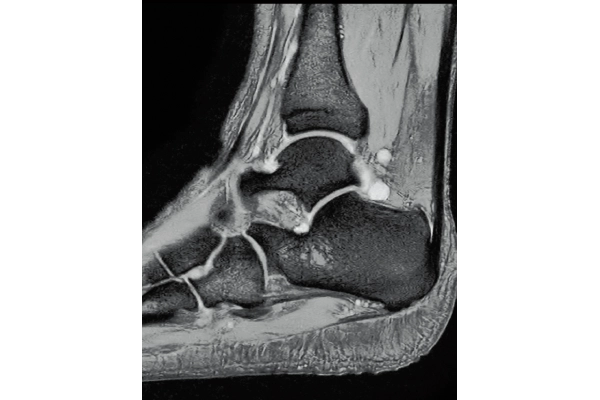

3D Bone

0.93×0.93×1.2(0.6)mm

1.1×1.1×1.2(0.6)mm

3DisoFSE T2WI

0.75×0.75×1.1(0.55)mm

MPR COR